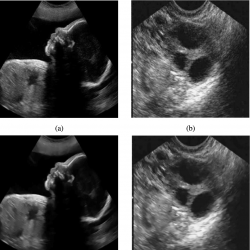

Fig. 9

Visual comparison of various speckle suppressing methods on two real ultrasound images. (a) and (b) Real ultrasound images. (c) and (d) The result of the proposed method.

In the second set, two other real ultrasound images, Fig.

9(a) and

9(b), from Siemens Healthcare (Siemens Healthcare GmbH,

2019), are considered and the proposed method is applied to reduce their speckle noise. The despeckled result of these images are shown in Fig.

9(c) and

9(d), respectively, which show that our proposed method can effectively suppress the speckle noises.

Generally, experimental results of the first and the second set of selected images illustrate that the proposed approach can obtain better performance in terms of PSNR and SSIM for ultrasound image denoising. From visual comparison, it is easy to see that our proposed method gets smooth effect while preserving the edges of images, which lead to maintain the useful texture information of test images.